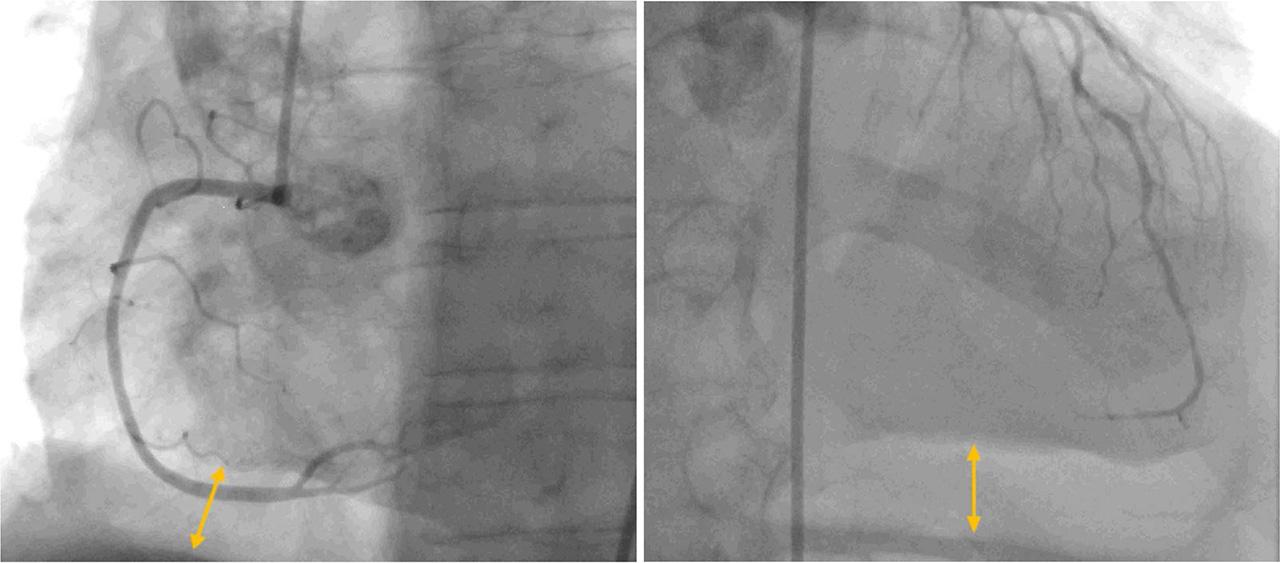

The patient underwent immediate coronary angiography. Obstructive coronary artery disease was excluded. However, a striking 20 mm hydroaeric image lining the inferior edge of the cardiac projection was visible (Figure 2). Following the angiography, an emergency chest CT scan was performed, which confirmed the hydropneumopericardium (the presence of air density of 13 mm and liquid of 18 mm in the pericardial cavity; Figure 3A), but also showed a circumferential thickening of the esophagus. Searching for a possible etiology, a Gastrografin study revealed a slight extravasation of contrast medium into the pericardial cavity, indicating a potential esophagopericardial fistula (Figure 3B). An emergency exploratory thoracotomy was performed to drain the purulent fluid from the pericardial cavity, but without revealing a fistulous path. After the procedure, the patient was transferred to the intensive care unit for monitoring and empiric antibiotic treatment.

Coronary angiography showing normal coronary arteries. Hydroaeric image lining the inferior edge of cardiac projection (arrows)